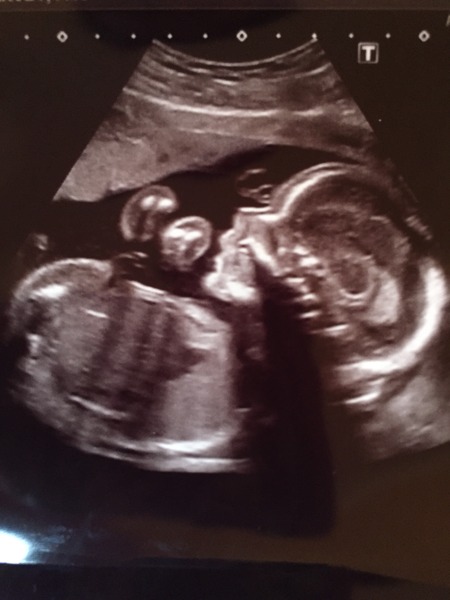

Paperblank · 19/10/2015 15:25

Here's baby Grin

Non- compliant just like it's mother ha ha

What a lovely clear scan pic Paper! Are you going to find out privately or keep it a surpise now?